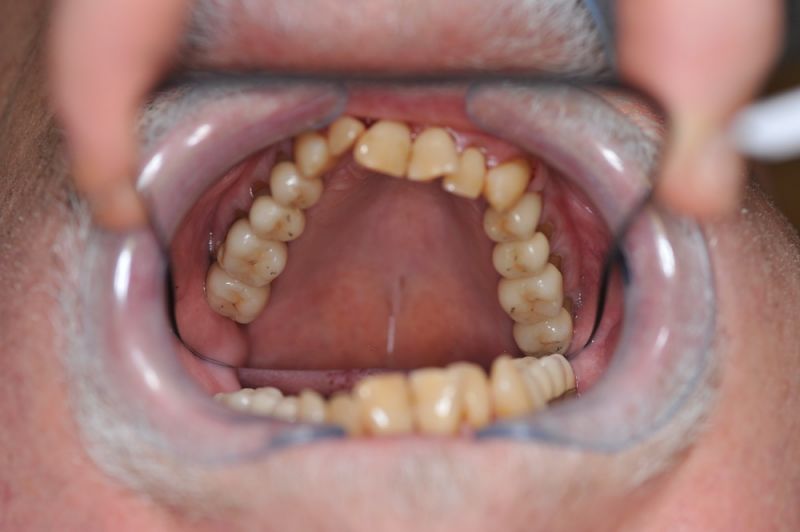

80 jähriger Patient aus Kiel erhält die beiden letzten Rekonstruktionen. Behandlung abgeschlossen

Der Patient erhält die beiden letzten Kronen zur Einstellung der dynamischen Okklusion.

In diesem Fall möglich über die Herstellung von zwei Eckzahnkronen